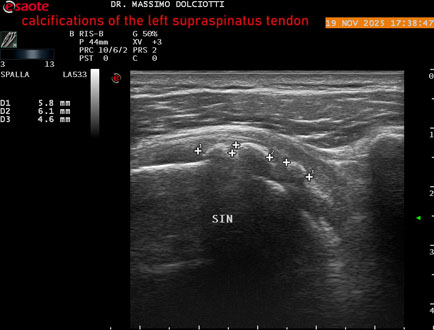

Ecografia del: 19/11/2025

Strumento: Esaote MyLab Eight

Sonda: Lineare Multifrequenza 3-13 MHz

Età Paziente: M 52 anni

Motivazione dell'esame: dolore alla spalla sinistra che peggiora con il freddo.

Commento all'esame: le immagini ed il video documentano il tendine sovraspinato sinistro disomogeneo per evidenza, in sede prossimale e mediale, di immagini iperecogene multiple, delle dimensioni di 5,8 mm - 6,1 mm - 4,6 mm da ricondurre a calcificazioni.

Conclusioni: calcificazioni del tendine sovraspinato sinistro (calcifications of the left supraspinatus tendon).